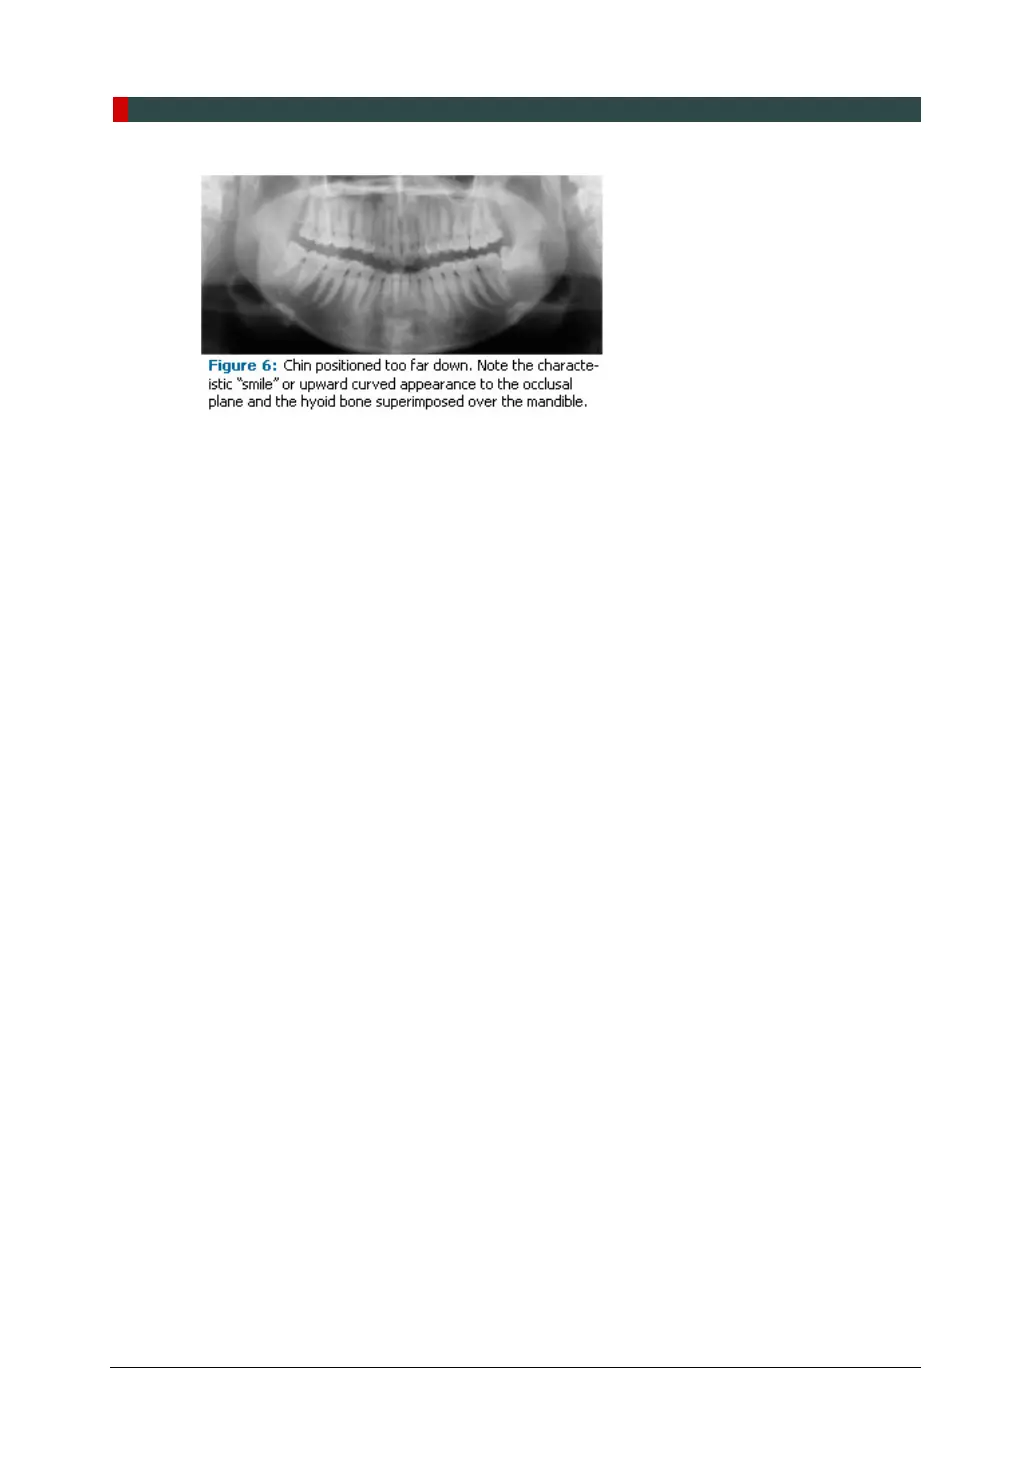

Correct positioning of the arches in the superior-inferior dimension requires that the patient

stands with erect posture while tucking the chin in and down slightly, a direction that both

adults and pediatric patients often find difficult to follow without specific guidance. The

result is often a slumped position with the patient hunching the neck and shoulders over in

an attempt to place the chin on the chin rest. The vertebrae collapse causing attenuation

of the x-ray beam that produces a triangular radiopacity superimposed over the mandible,

and if severe, over the anterior maxillary regions as well.